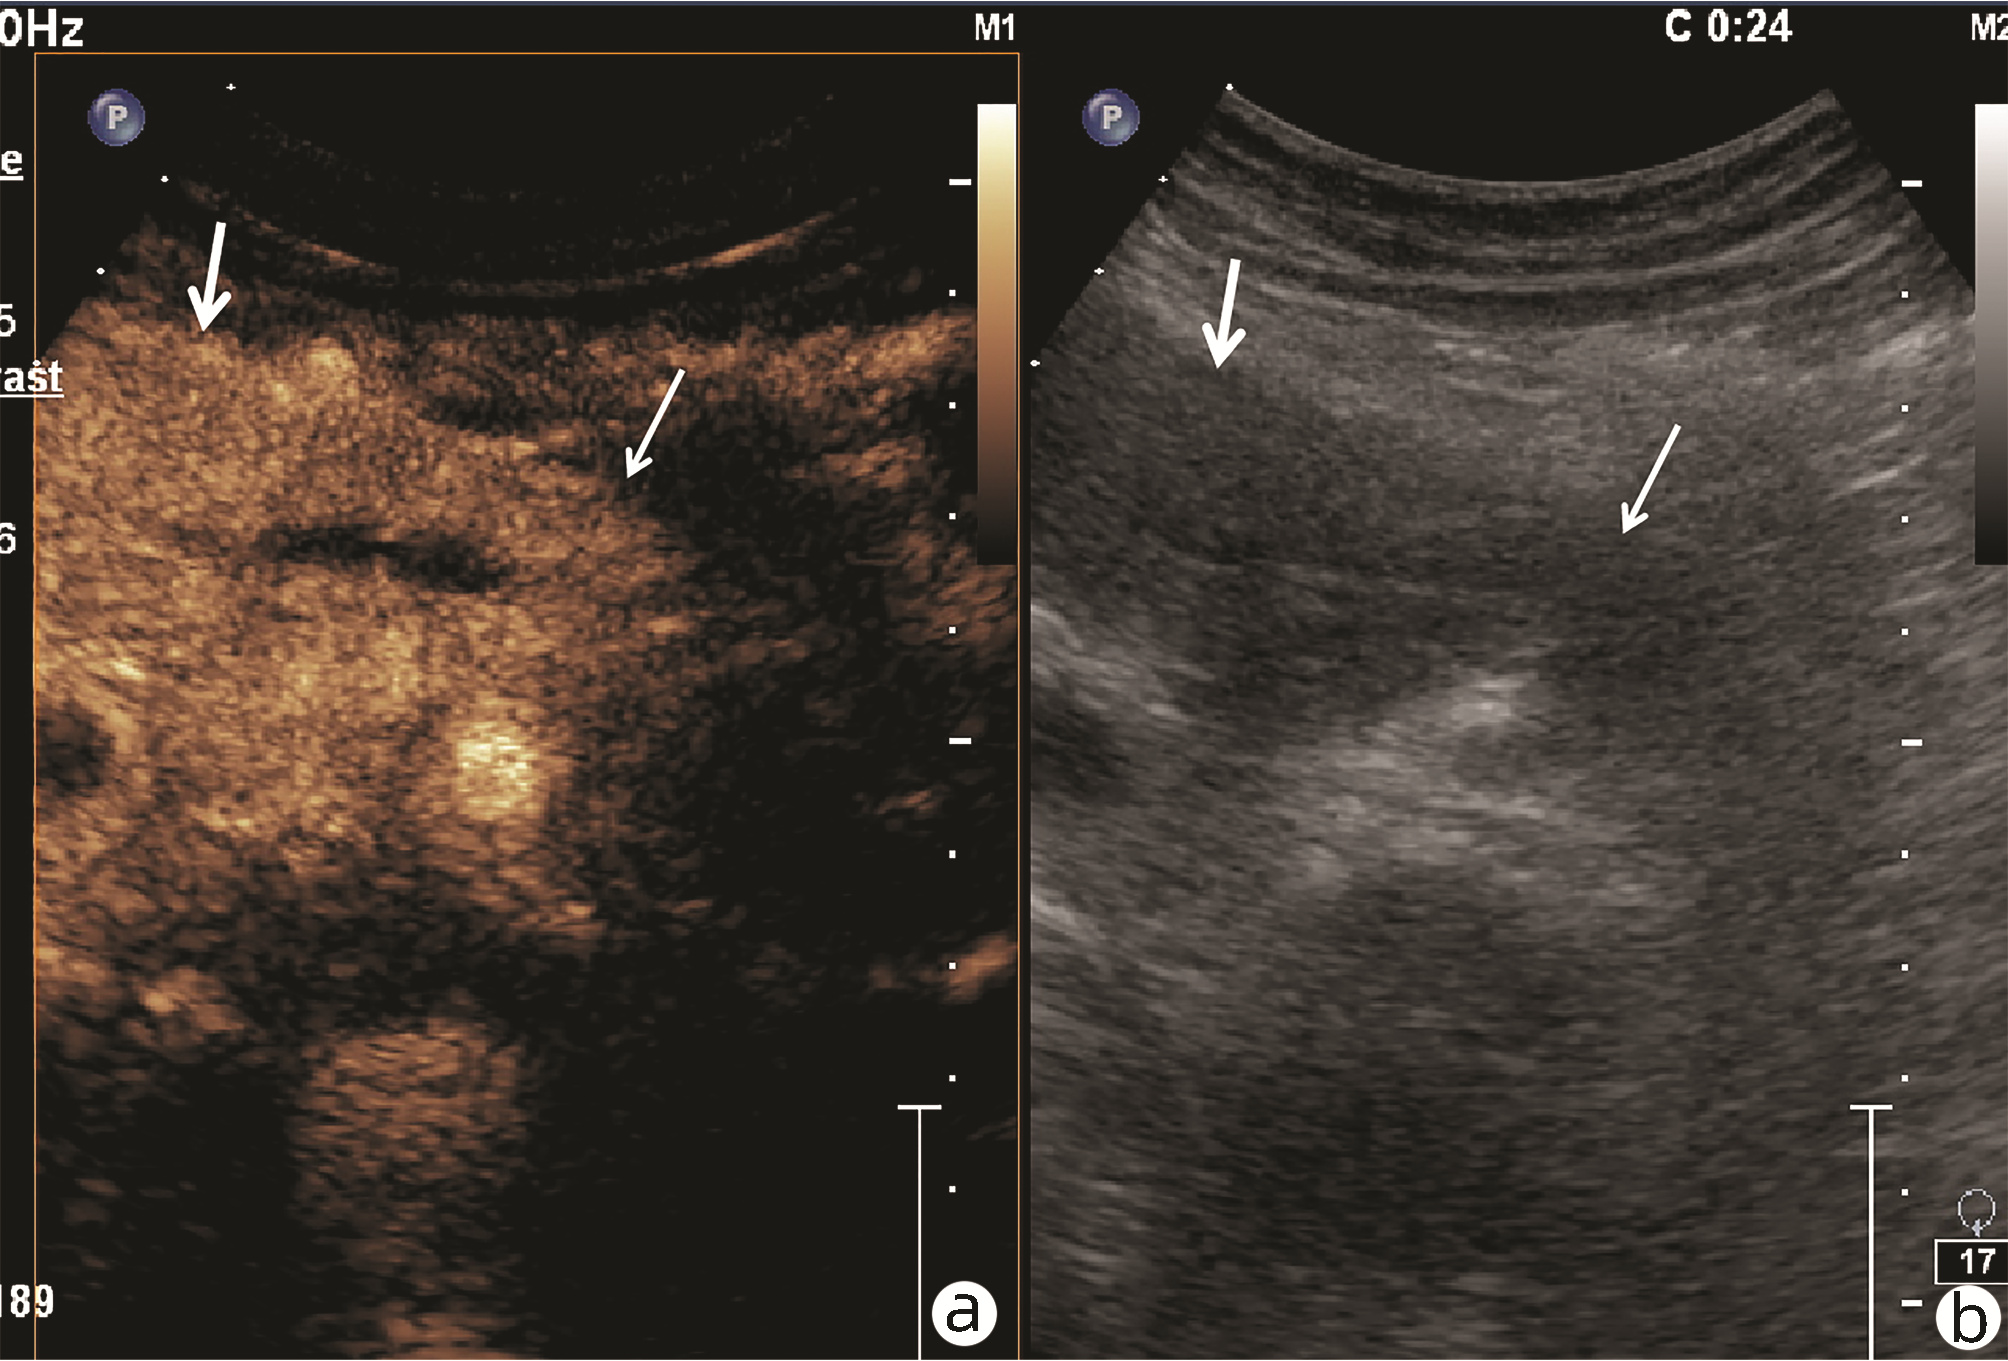

肿块型自身免疫性胰腺炎与胰腺导管腺癌的超声及超声造影表现分析

欧阳向柳, 韩云霞, 郑立春, 赵英春, 申新宇, 张文军, 王艳滨

2022, 38(6): 1351-1355. DOI: 10.3969/j.issn.1001-5256.2022.06.025

摘要(1431) HTML (553) PDF (3738KB)(51)

摘要:

目的  探讨超声及超声造影对肿块型自身免疫性胰腺炎(AIP)与胰腺导管腺癌(PDAC)的鉴别诊断价值。  方法  回顾性分析2015年1月—2020年12月唐山市工人医院确诊的11例肿块型AIP患者的临床资料及常规超声、超声造影资料,分析其特征性表现,并与23例PDAC患者的资料进行对比,计数资料两组间比较采用χ2检验。  结果  11例肿块型AIP超声造影的诊断准确性为63.64%,均为单发病灶,且均低回声,在边界清晰、形态规则、胰管扩张或截断、血流信号方面所占比例分别为54.55%、63.64%、18.18%、36.36%,而PDCA组分别为30.43%、34.78%、78.26%、21.74%,两组间是否伴胰管扩张或截断方面存在统计学差异(χ2=11.089,P<0.05),其余指标均无明显统计学差异(P值均>0.05)。超声造影中7例(63.64%)肿块型AIP动脉期呈高增强,4例(36.36%)呈等增强,静脉期5例(45.45%)呈高增强、6例(54.55%)呈等增强;23例PDAC中22例(95.65%)病灶在动脉期及静脉期均呈低增强,两者动、静脉期强化方式差异均有统计学意义(χ2值分别为30.345、30.084,P值均<0.05)。  结论  超声造影检查增强模式及是否伴胰管扩张或截断方面在肿块型AIP与PDCA的鉴别诊断中具有较高的价值。